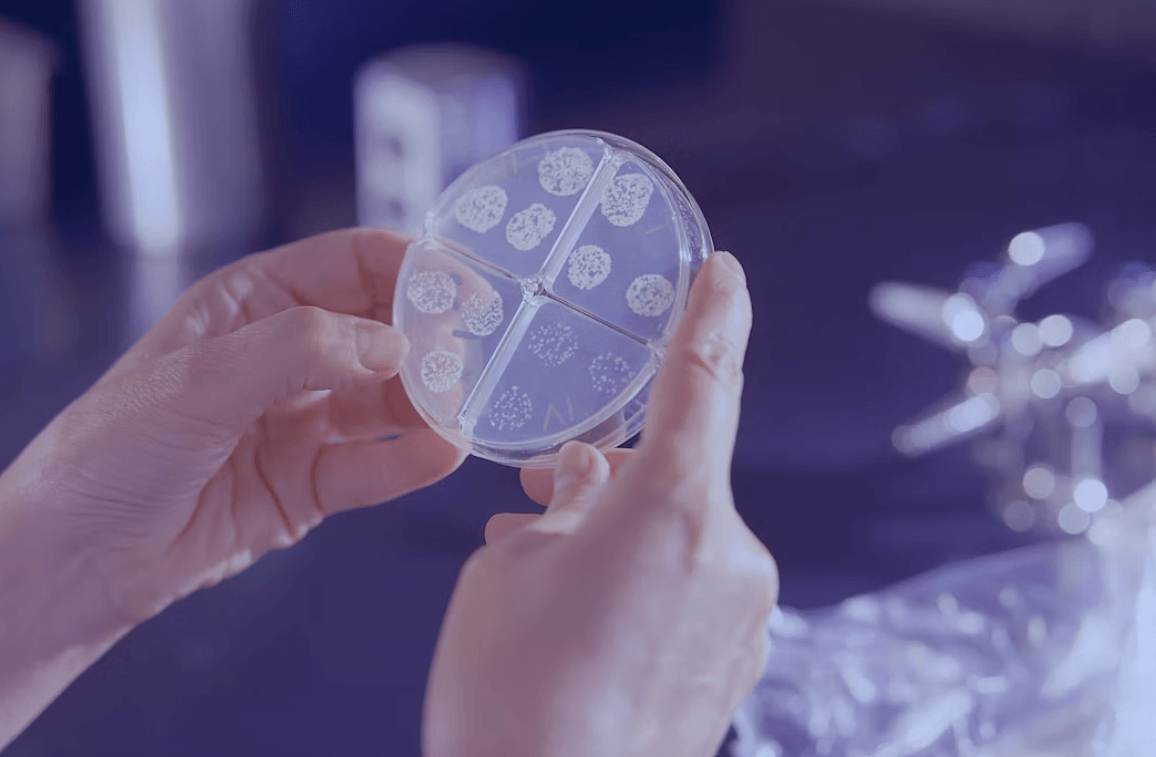

Una reciente evaluación de productos proteicos de venta libre encontró presencia de metales pesados en la mayoría...

Un equipo de científicos utilizó tecnología avanzada para identificar alteraciones genéticas. Cuáles fueron los resultados que publicaron...

La secuenciación completa del genoma podría transformar la atención del cáncer de mama al identificar alteraciones genéticas...